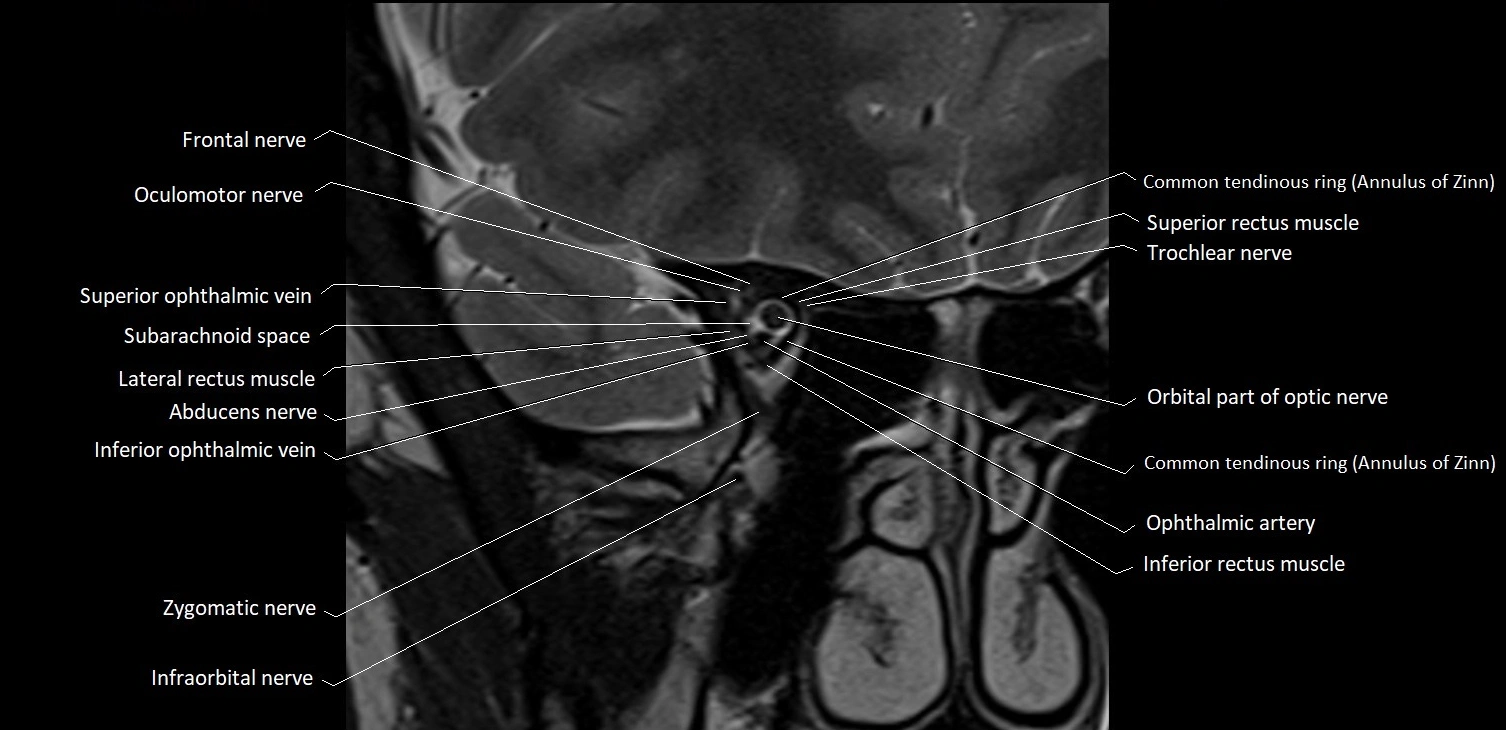

MRI images